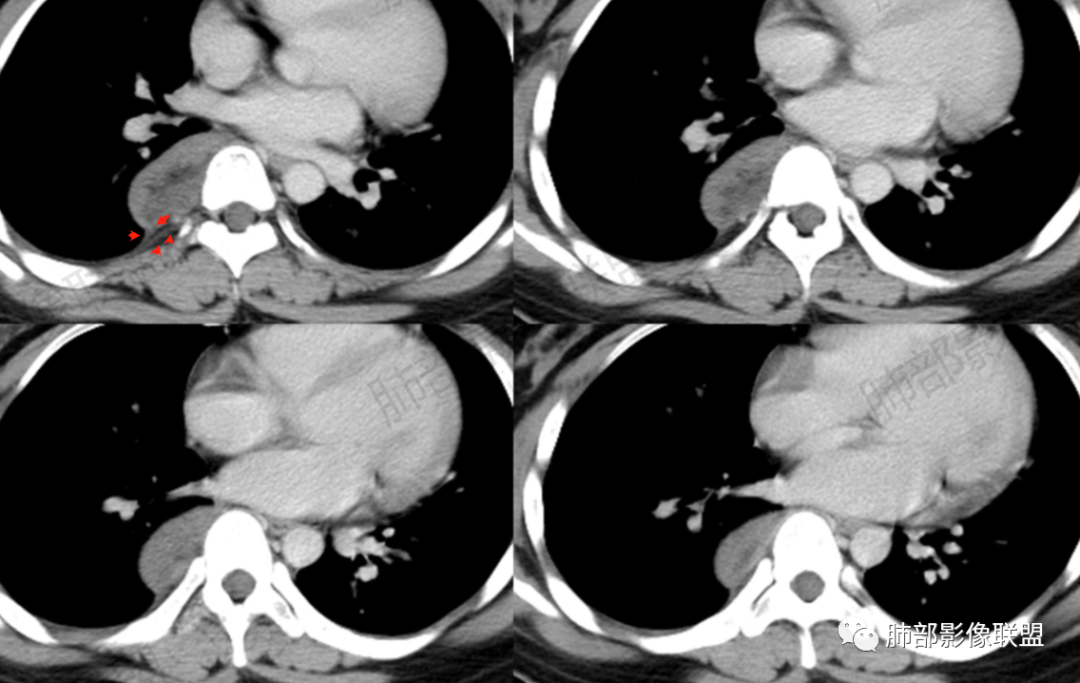

CT值平扫33HU,增强:45HU左右

定在轻度强化

2.肿块含脂肪等成分,与交感神经路径相一致,渐进性轻度强化(可能含有粘液成分)等,以节细胞神经瘤最可能!尽管未显示“习惯性”的钙化。

CT上大部分的后纵隔神经节细胞瘤呈较均匀性低密度或稍低密度影,低于肌肉密度,这主要是由于瘤体的密度根据其内含有不同比例的黏液基质与节细胞纤维成份而不同,cT值一般约20~40 HU 但其多数密度均匀,部分甚至可接近囊性低密度,这与组织学上神经节细胞胞浆丰富,瘤内含有大量黏液基质相关。MRI 上后纵隔神经节细胞瘤多呈 T1wl 低信号T2wl稍高/高信号,其中夹杂的低信号多为胶原纤维或施万细胞成分,这些低信号可纵横交错分布呈曲线或线状,这可认为是神经节细胞瘤的特征性MR表现,本组3例可见该征象。有学者报道,部分神经节细胞瘤可出现脂肪密度信号影,后纵隔肿瘤内出现脂肪密度/信号是诊断神经节细胞瘤的一种较特异性表现。神经节细胞瘤的钙化率20%~42%,钙化多呈斑点状,很少出现不规则或不均质的形态,散在点状或沙粒状是神经节细胞瘤的特征,而粗大条状或不定形则倾向恶性。

(3)增強:

后纵隔神经节细胞瘤常动脉期无明显強化、或轻度间隔、包膜或瘤体强化,延迟期可进一步斑片、结节状轻度或中度强化,强化程度进行增加,呈渐进性延迟强化,但強化程度一般为轻度到中度强化,究其原因可能是神经节细胞瘤瘤体内含有大量黏液基质和胶原纤维,使得细胞外间隙扩大,阻碍了对比剂的灌注,从而延缓了对比剂的积累,因此其动脉期多无明显强化或仅有轻度强化,延迟期呈渐进性轻度强化是后纵隔神经节细胞瘤强化特征。大部分病灶有轻度-中度强化,部分病灶无强化,这还可能与瘤组织内部间质血管含量多少相关,无强化病例瘤组织内部主要由胶质纤维和节细胞组成,间质血管较少,因此强化较低,而强化程度较高的病理可见较多的扩张、充血的毛细血管,引起较多的对比剂积蓄,因此强化相对明显。因此,神经节细胞瘤极少出现瘤组织早期强化,而多呈延长渐进性强化,增强扫描神经节细胞瘤内细胞成分可增强,黏液基质不强化。